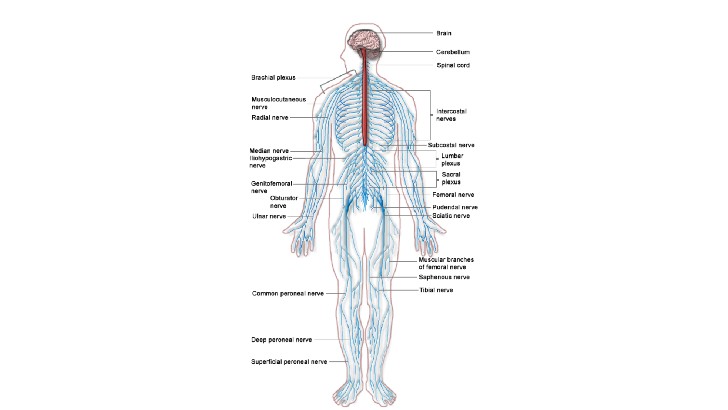

From the peripheral nervous system to the central nervous system, sensory neurons conduct impulses. Motor neurons transport signals from the central nervous system to muscles and glands. Between sensory and motor neurons, what kind of neurons are found?

Intraneurons

Ectoneurons

Interneurons

Paraneurons

Which of the following is the body’s single longest nerve?

Ulnar nerve

Sciatic nerve

Solar plexus

Radial nerve

What causes multiple sclerosis symptoms?

Degeneration of the sheath that covers the neurons of the central system and the replacement of this sheath with scar tissue.

Excessive neurotransmitter release.

Multiple sclerosis is caused by obesity.

Excessive carbohydrate intake.

A reflex is which of the following?

Getting angry

Chewing food

Dilation and constriction of the pupils

Finger tapping when nervous